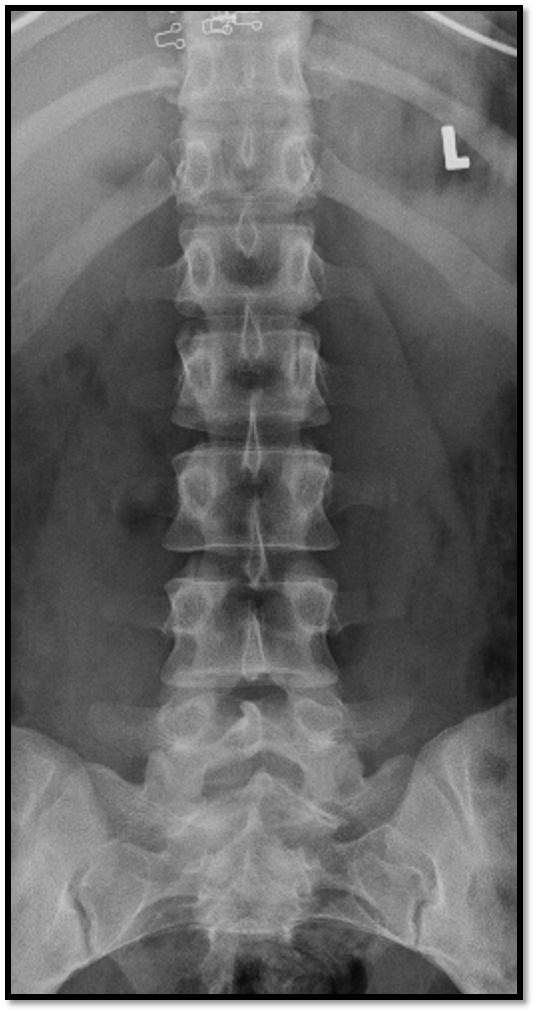

AP Lumbar Spine

A

• spinous processes are midline

• open disc spaces

• T10-S1 included

23

Q

pelvis is rotated in an LPO position

24

pelvis is slightly LPO and knees could be flexed to flatten spine out